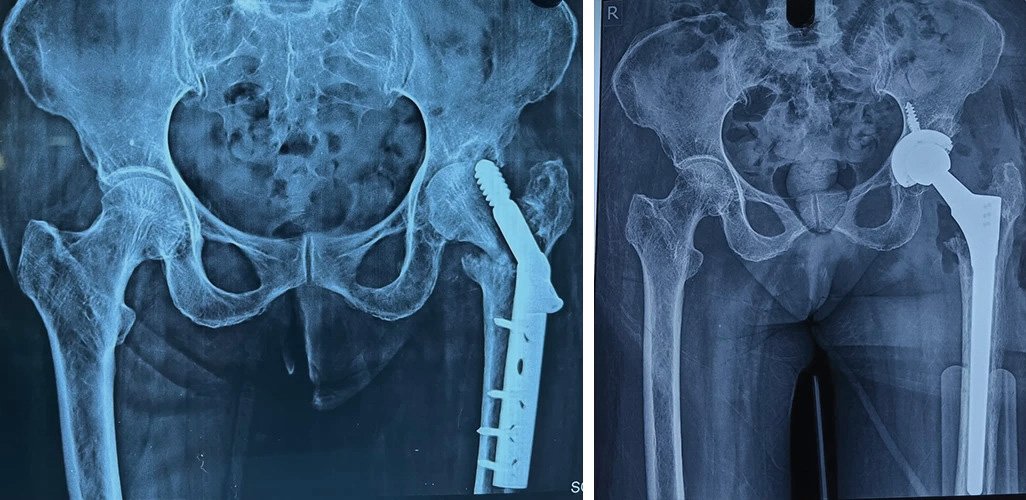

Total Hip Replacement

Are your hips causing you constant discomfort? If you're tired of living with hip pain, Dr. Prasun Sanyal is your best solution.